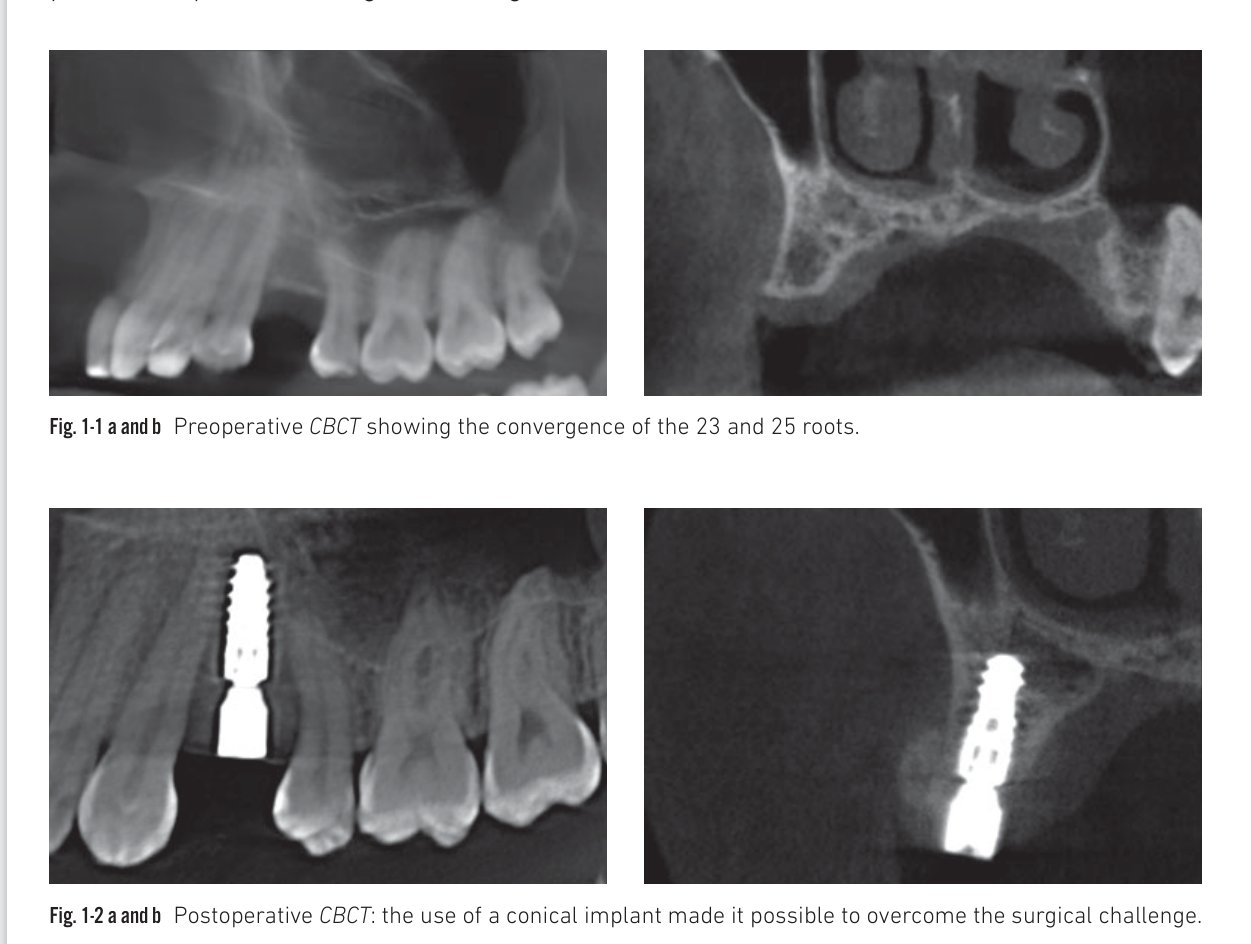

The management of narrow spaces due to converging roots

The pre-implant analysis systematically includes radiographic analysis. The presence of converging roots is detectable on peri-apical X-rays and CT scan. The bone volume available for implantation is sometimes reduced by adjacent converging roots; damage to the cementum or dentin caused by drilling can trigger external resorption, fracture, or even necrosis. When the residual volume is too small to guarantee a safe distance from anatomical obstacles, it is a local contraindication and pre-implant orthodontic treatment is necessary. In less clear-cut situations, the use of an implant with apical conicity — such as the BLX — saves space and allows placement in the desired position while avoiding adjacent roots.

Clinical situation 1: CBCT views showing converging roots and conical implant placement